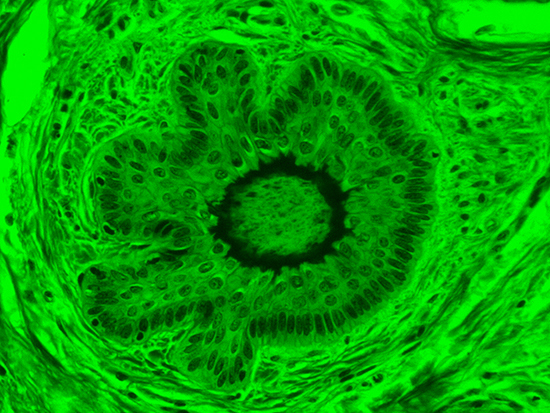

Figure 3: Brightfield Image of Dermal Tissue filtered with Green

When comparing Figure 3 with Figure 4, there is once again a significant visual difference. The most obvious feature is the change in color from green to red due to a different hardcoated filter being positioned in the optical path. The less obvious difference is the varying contrast levels caused by the filters at specific regions of the dermal tissue. For example, Figure 3 exhibits a distinct ring at the central region of the cell with additional matter within. In Figure 4, the ring is extremely faint and the internal matter is not visible. With that said, the cell and surrounding dense materials are more evident in Figure 3, whereas the muscle fibers and collagen are more pronounced in Figure 4.